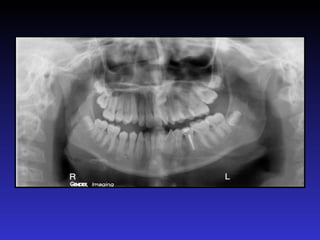

Tiêu chuẩn phim đúng

• Đường giữa răng cửa hàm dưới trùng với đường giữa răng cửa hàm

trên

• Đường nối liên tục giữa rìa các răng cửa trên có hình dáng của đường

cười

• Xương móng hai bên cân đối

• Xem được rõ nét hai cung răng, xương hàm dưới và đáy xoang hàm

Đánh giá phim panorama chuẩn